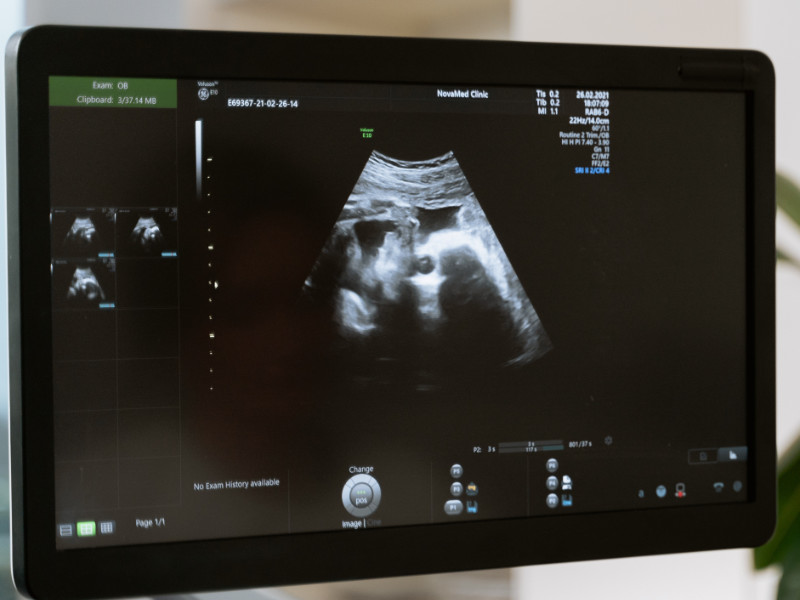

L'échographie est un examen médical d'imagerie à ultrasons non douloureux pour le bébé et la maman. Elle permet de suivre la croissance de votre fœtus pendant la grossesse.

C'est l'écho dite morphologique, à travers diverses mesures; tête, abdomen, fémur, est estimé le poids.

Sont vérifiés également le développement de ses organes, sa croissance, sa vitalité et votre liquide amniotique.